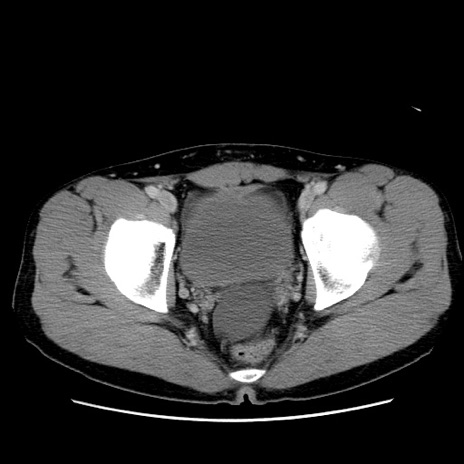

症例36(横断像)

【症例】20歳代 男性

【主訴】心窩部痛

【現病歴】今朝より上腹部痛あり。一旦軽快していたが再度出現したため救急要請。昨日夕に白身の魚を含む刺身を食べた。

【身体所見】BP 136/89mmHg、HR 74/min、BT 37.0℃、腹部:膨満、軟、心窩部に圧痛あり。反跳痛なし、筋性防御なし、腸雑音やや亢進あり。

【データ】WBC 17700、CRP 0.48